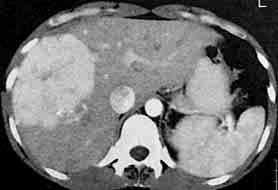

增强扫描延迟20秒显示两个明显强化的病灶,内有中心瘢痕.